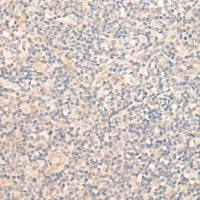

| Applications: | ELISA,WB |

| Immunogen: | SyntheticpeptideofhumanZNF365 |